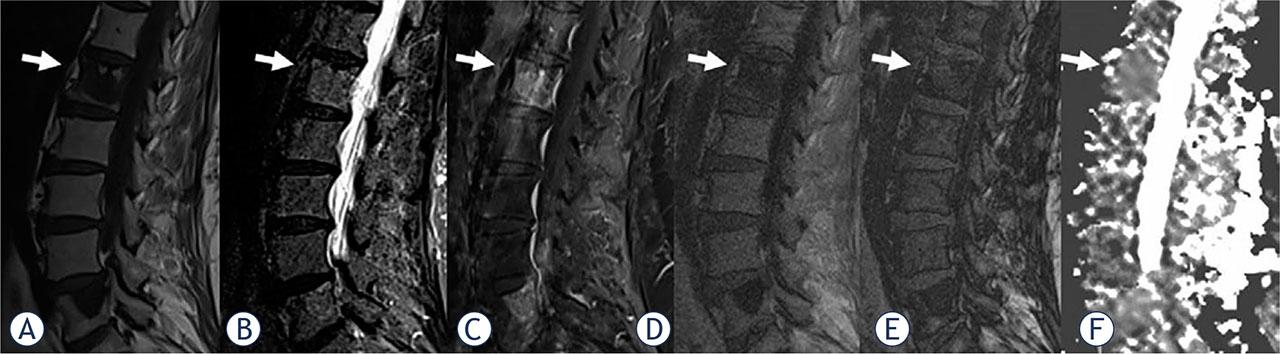

FIGURE 2.